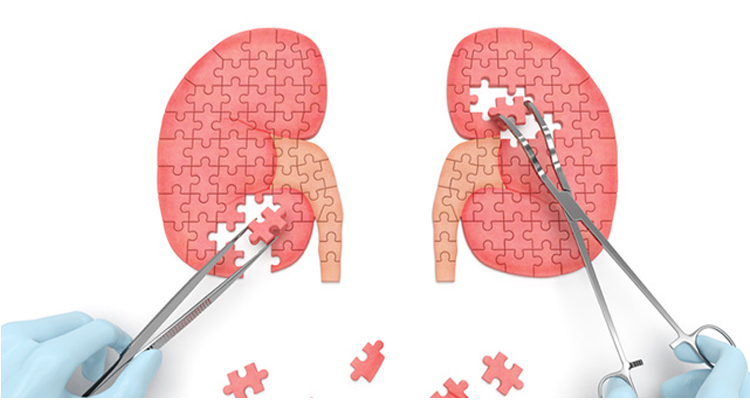

Chronic Kidney Disease (CKD) Management

Managing Chronic Kidney Disease (CKD) involves a comprehensive approach. Lifestyle modifications, such as a low-sodium diet and regular exercise, support kidney health. Blood pressure and blood sugar control are crucial in slowing CKD progression. Medications, like ACE inhibitors or angiotensin II receptor blockers, may be prescribed to manage blood pressure and protect the kidneys. Regular monitoring of kidney function, dietary adjustments, and collaboration with nephrologists contribute to effective CKD management, aiming to delay disease progression and prevent complications

Acute Kidney Injury (AKI) Treatment

The treatment of Acute Kidney Injury (AKI) involves addressing the underlying cause and providing supportive care. Identifying and resolving factors like dehydration, infections, or medication-related issues is essential. In severe cases, hospitalization and interventions, such as intravenous fluids and medications to support kidney function, may be necessary. Close monitoring of fluid balance, electrolytes, and kidney function is crucial throughout the treatment process. Collaborating with healthcare professionals ensures a tailored approach, aiming for timely recovery and preventing complications